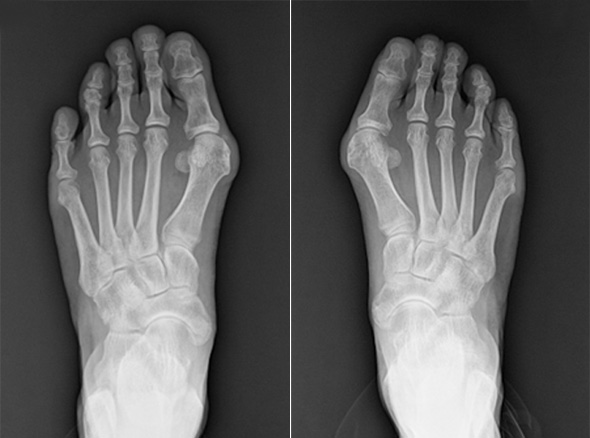

부모님이 무지 외반증을 가지고 있을 때, 발볼이 넓은 유연한 발을 가지고 있을 때 무지외반의 발병이 흔하며,

청소년기에 보이는 무지 외반증은 유전적인 요인 때문이라고 볼 수 있습니다.

뼈의 변형이 원인이기 때문에 교정기 등은 효과가 없는 것으로 알려져 있으며,

증상 호전을 위해 발볼이 넓은 신발을 신는 등의 교정을 먼저 시도해볼 수 있습니다.

만약 증상이 심하고 호전되지 않을 때 수술적 치료를 고려하게 됩니다.